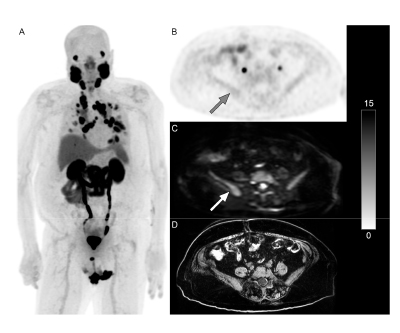

PET/MRI with metastases, minimal PSMA activity in pelvic bones, but osseous metastases,  and a T1-weighted image. Figure 2.

Adding whole-body diffusion-weighted imaging (WB DWI) to PSMA PET scans for patients with metastatic castration-resistant prostate cancer can allow radiologists to identify PSMA-negative lesions, potentially altering their treatment plan. The most common locations for these lesions were the lymph nodes followed by bones and, less frequently, the lungs and liver.

This research was published in the Journal of Clinical Medicine in March 2025.

Authors: Cheng William Hong, Spencer Behr, Fei Jiang, Yingbing Wang, Sina Houshmand, Thomas Hope